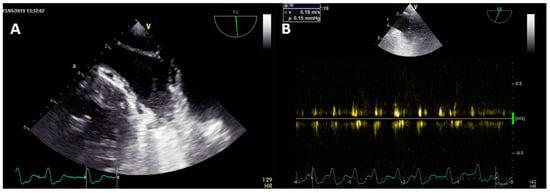

3.2. Transesophageal Echocardiography and Intracardiac Echocardiography